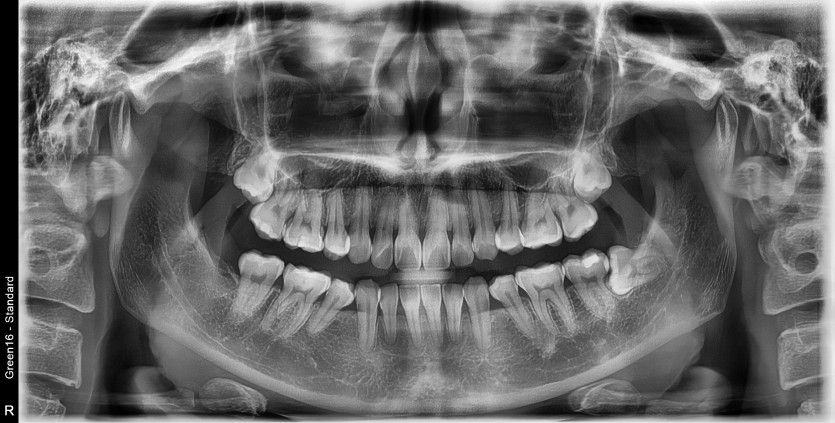

#38 사랑니 발치

구강 외과 전문의가 당일 발치했습니다.